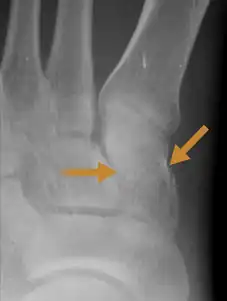

An X-ray of a Medial cuneiform fracture

A Cuneiform fracture is an injury of the foot in which one or more of the Cuneiform bones are fractured.[2] The annual incidence of cuboid fracture is 1.8 injuries per 100,000 population.[3]

Cuneiform fractures can be very difficult to diagnose because of the complex overlapping articulations of the midfoot, which can make them invisible on plain films. Therefore, identification might need for more sophisticated imaging, like CT or MRI.[6]